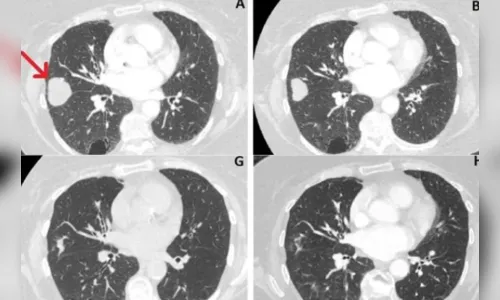

Autor Imagens do exame mostram que tumor diminuiu de cerca de 41 mm para 10 mm - Foto: Metrópoles

Imagens de exames mostram que o tamanho do tumor diminuiu de 41 mm, em junho de 2018, para 10mm, em março de 2021. Ou seja, uma redução de cerca de 76%.